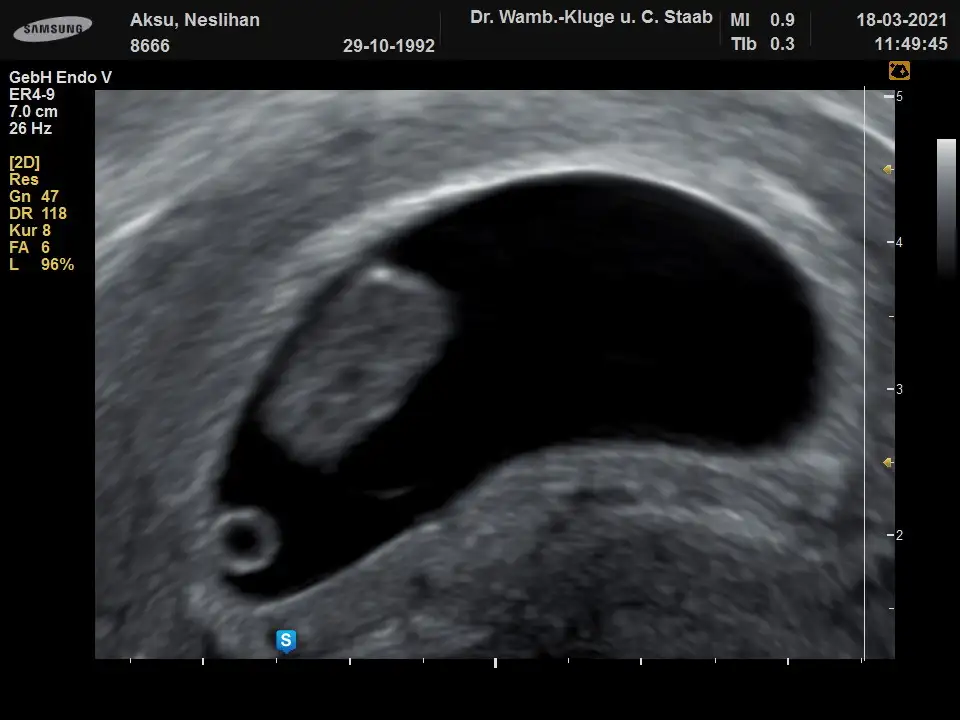

Canim banada bakabilirmisnn 9.hafta vajinal ultrasyonOzmaan erkek görünüyor